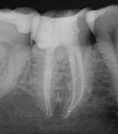

Long Term CaOH Cases

12 Month CaOH Treatment

14 Months CaOH Treatment